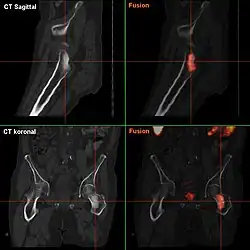

- F-18-Cholin-PET/CT

-

Osteolytische Knochenmetastase im zweiten Halswirbelknochen (Axis) eines metastasierten Prostatakarzinoms -

Osteoplastische Knochenmetastase eines metastasierten Prostata-Karzinoms im Hüftgelenk -

CT einer Prostatakrebs-Metastase im linken Schambein (im Bild rechts) -

Cholin-PET derselben Metastase im Schambein -

Fusionsbild aus CT und Cholin-PET der Prostatakrebs-Metastase im linken Schambein